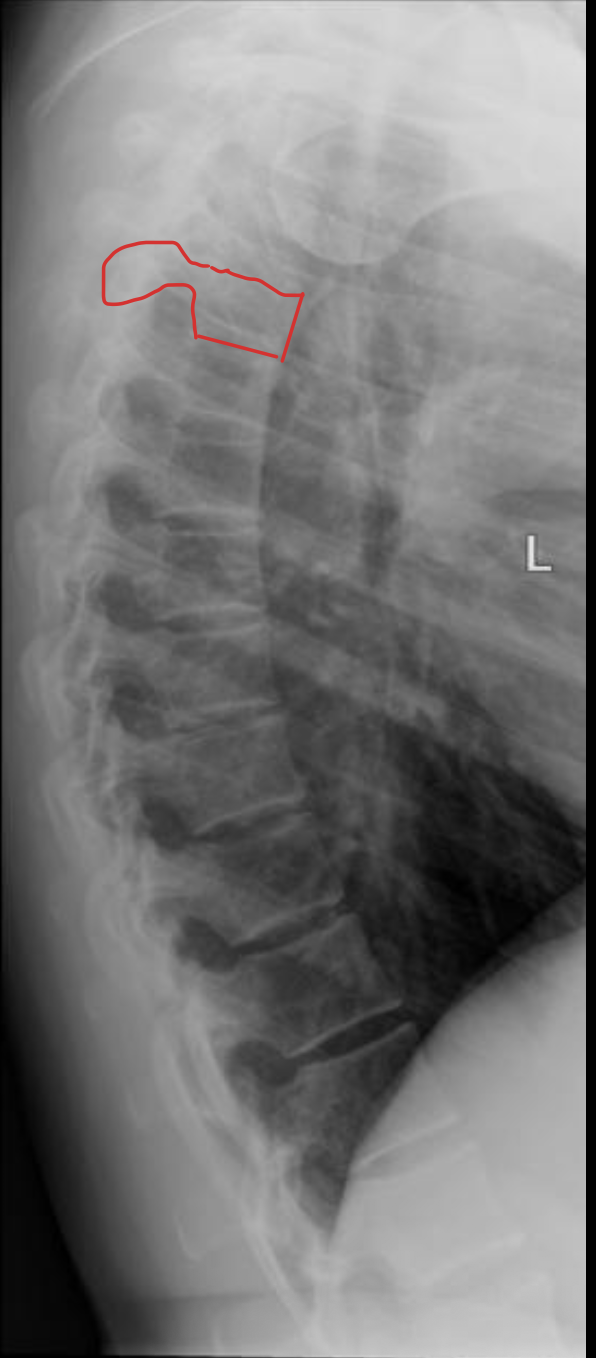

胸椎 12 块

Thoracic vertebrae

胸椎

THORACIC

T1

T2

T3

T4

T5

T6

T7

T8

T9